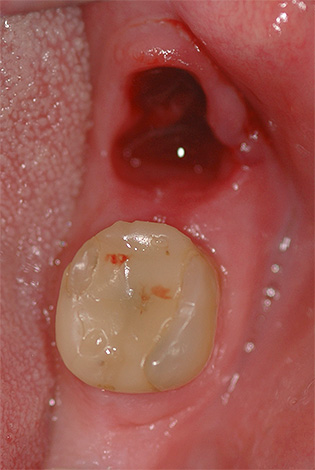

A foto abaixo mostra como o buraco fica logo após a remoção do dente do siso, anteriormente escondido sob a gengiva:

O coágulo sanguíneo que se formou após a extração do dente muda em alguns dias, da Borgonha para a mais clara, com um tom amarelado. A cor, neste caso, é determinada por processos fisiológicos naturais: o componente vermelho dos glóbulos vermelhos (hemoglobina) é gradualmente lavado pelo fluido da cavidade oral, mas o chamado esqueleto de fibrina é preservado, que serve como base estrutural do trombo, o que evita o sangramento do orifício do dente extraído.

Apesar da cor característica, você não deve confundir um coágulo sanguíneo normal com pus e temer que uma mudança de cor de Borgonha para mais clara já seja um sinal de alveolite. Além disso, você não precisa subir na ferida, pois isso pode danificar seriamente a cicatrização normal do buraco.